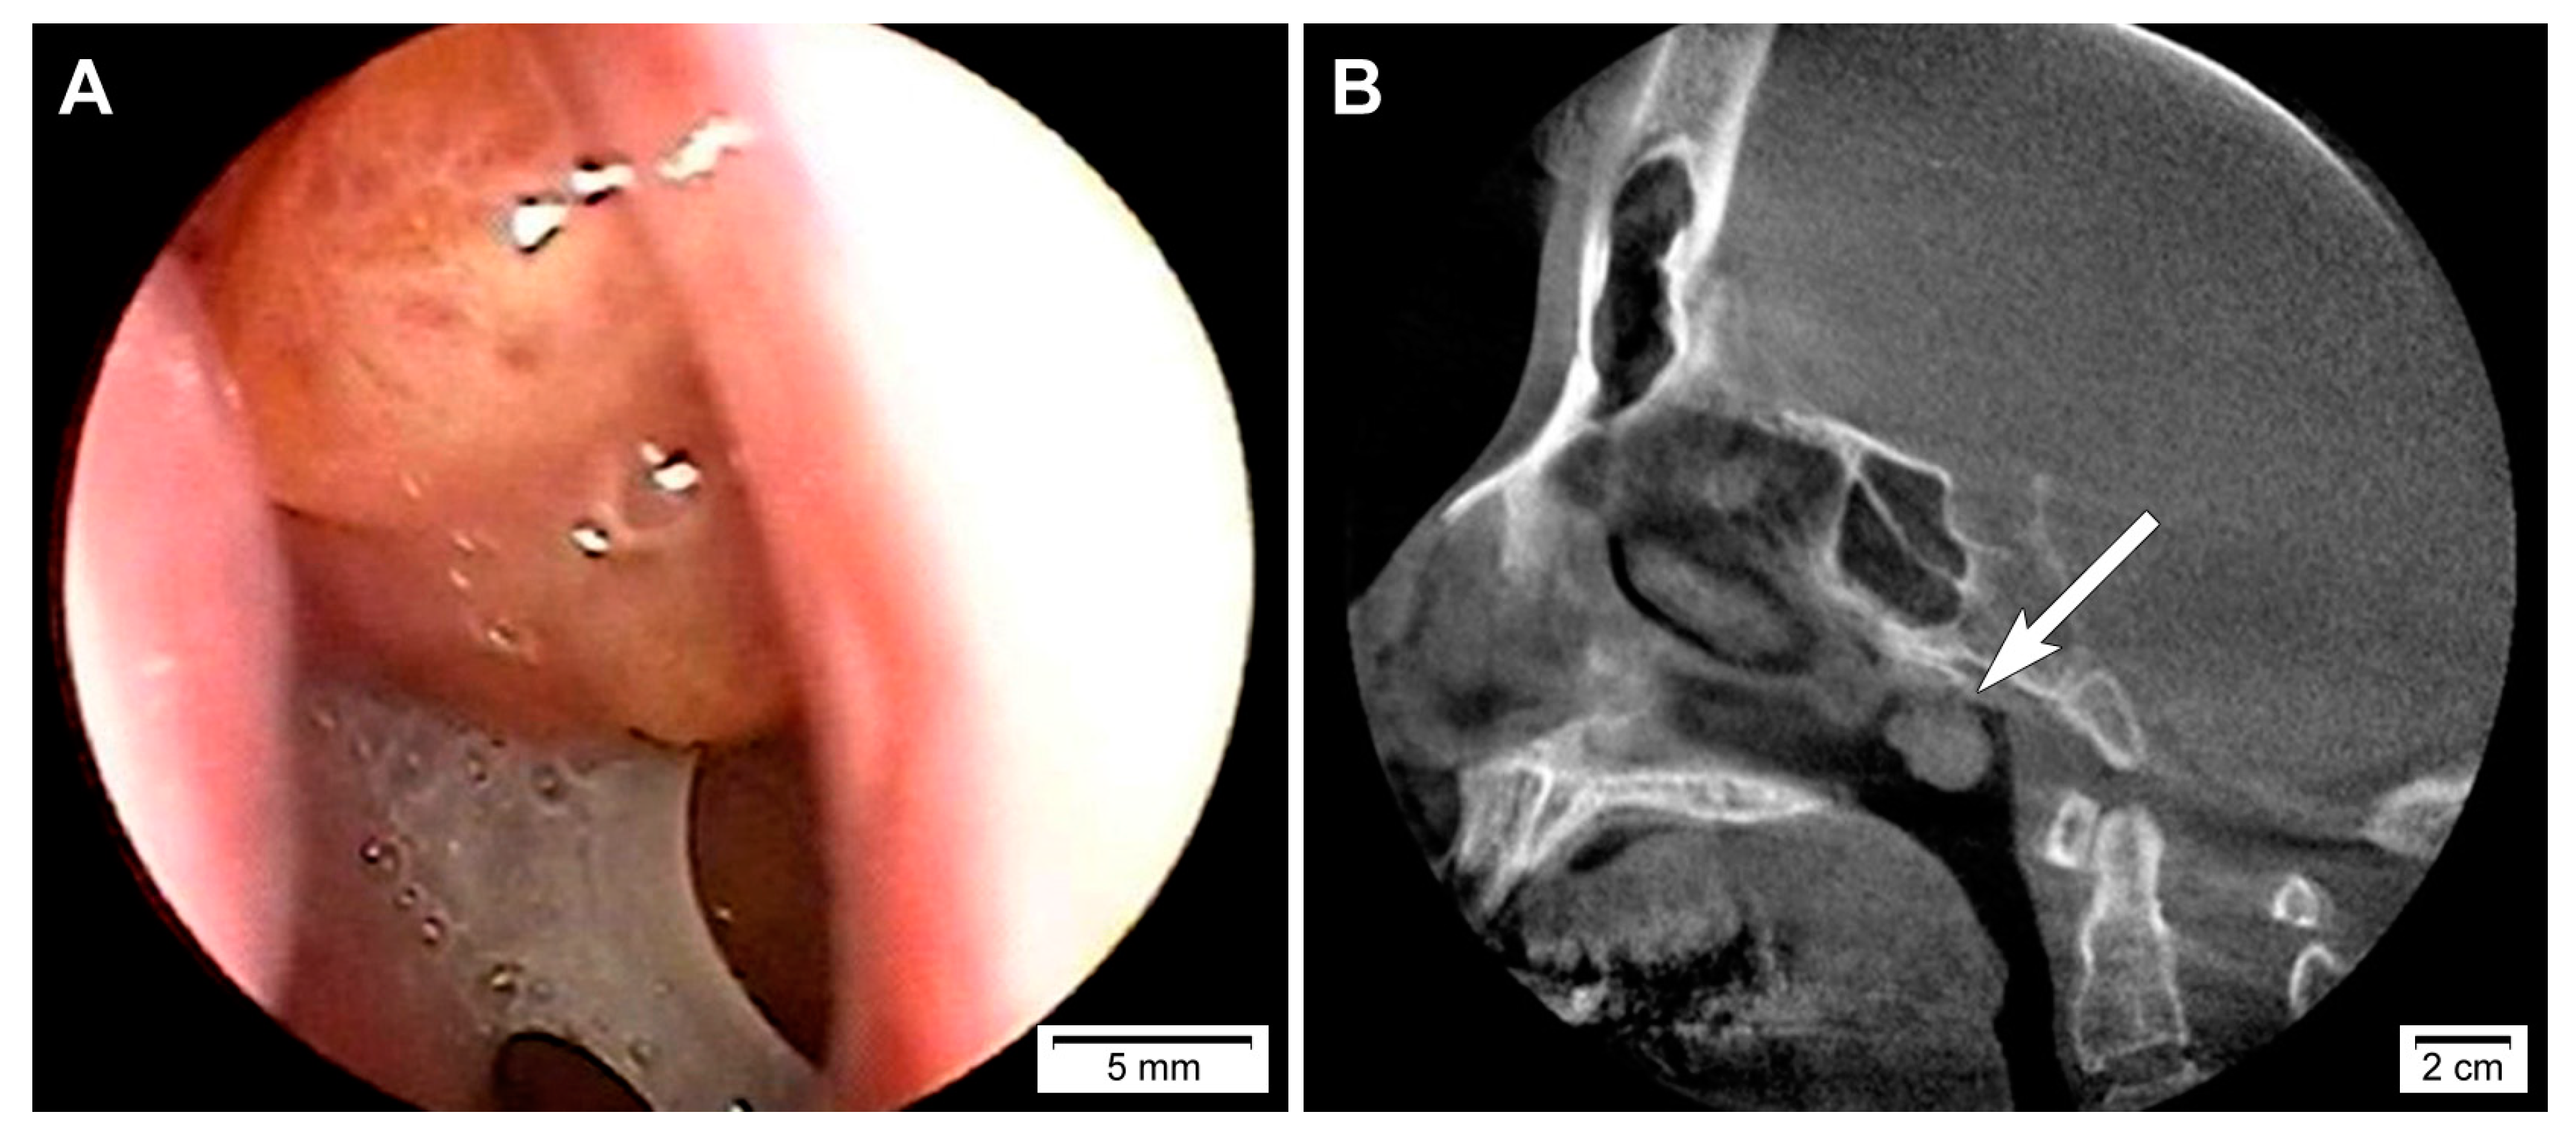

This study (2020-05-104) was reviewed and approved by the Institutional Review Board of Samsung Medical Center (Seoul, Republic of Korea). A 50-year-old woman presented with a sensation of a foreign body in the nasopharynx which she had never experienced before. Physical examination revealed no obvious abnormality. Nasopharyngoscopy (Figure 1A) and computed tomography scan (Figure 1B) revealed a pedunculated mass arising from the roof of the nasopharynx. Thyroid ultrasonography did not reveal any remarkable findings. Based on the clinical impression of a nasopharyngeal tumor, an excisional biopsy was performed. Written informed consent could not be obtained for the publication of this case report and its accompanying images because the patient was referred to another tertiary hospital immediately after the diagnosis.

Figure 1.

Imaging findings of biphasic thyroid-like low-grade nasopharyngeal papillary adenocarcinoma. (A) Nasopharyngoscopy and (B) computed tomography scan revealed a pedunculated mass arising from the roof of the nasopharynx (long white arrow).